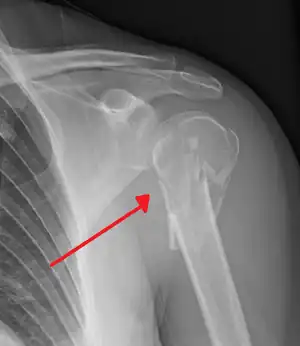

Surgical neck

The surgical neck is a narrow area distal to the tubercles that is a common site of fracture. It makes contact with the axillary nerve and the posterior humeral circumflex artery.

Fracture of the proximal humerus